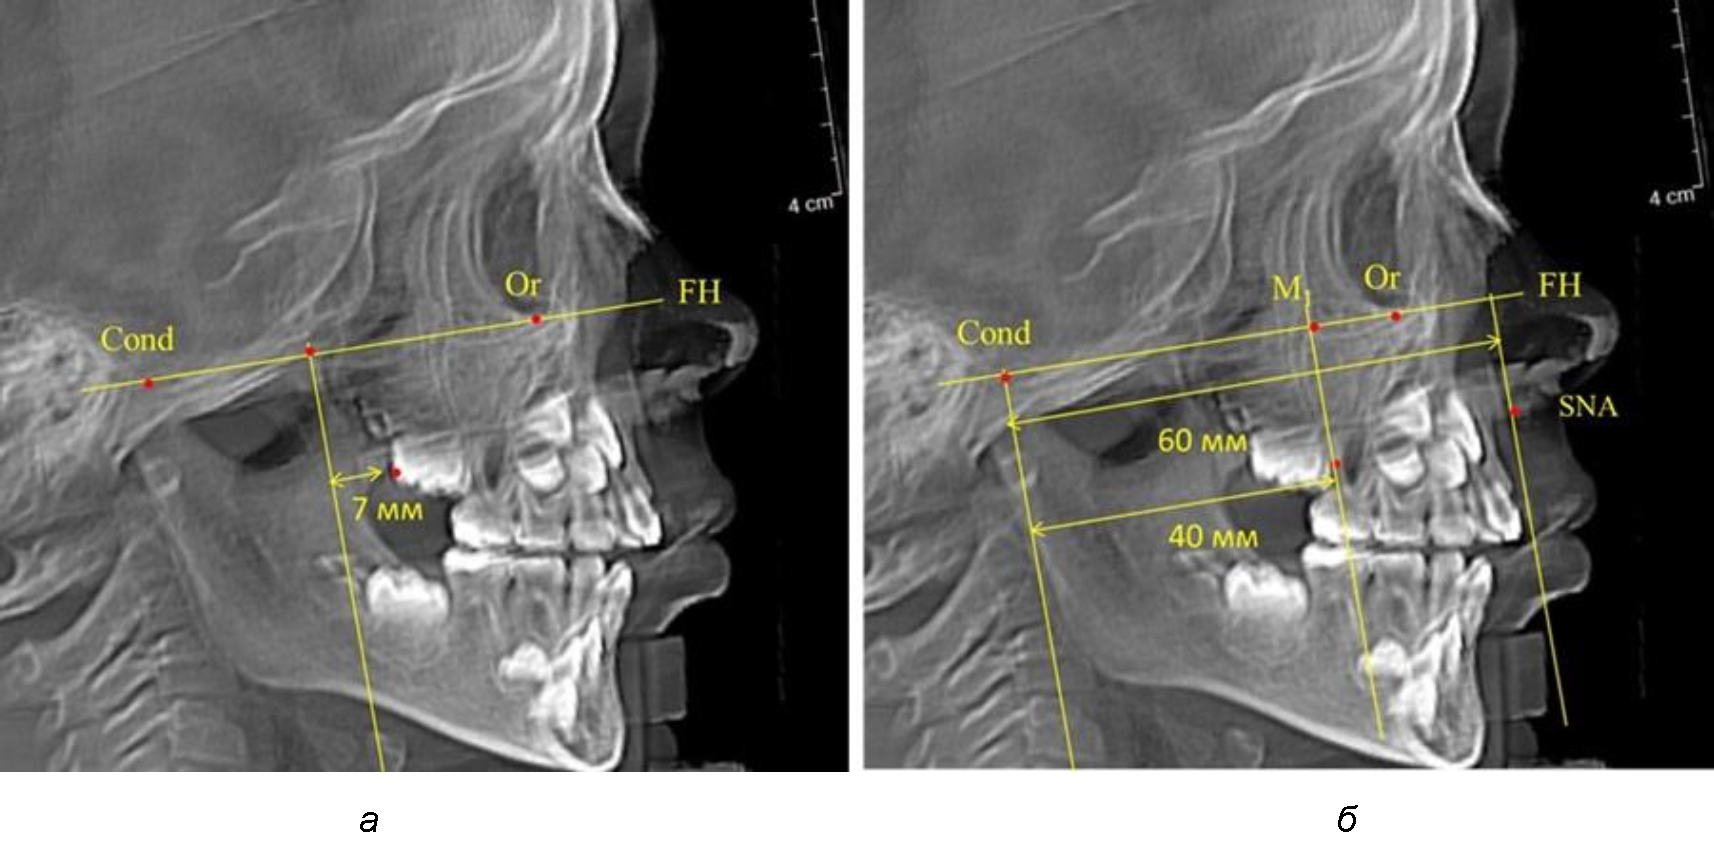

После прорезывания вторых постоянных моляров кондилярно-спинальный увеличивался до 80 мм.

Дистальная поверхность первого постоянного моляра отстояла от крыловидной вертикали на величину, составляющую около 18 мм, что, так же, как и в предыдущих периодах прикуса, было близким по значению к данным R. E. McDonald, а именно возраст, плюс 3 мм.

Обращает на себя внимание отношение глубины гнатического отдела лица к дистальному отделу, а именно к кондилярно-молярному расстоянию, которое, вне зависимости от сагиттальных размеров, составляло 1 : 1,5.

Рентгенограмма 16-летнего ребенка, с реперными линиями и анализируемыми линейными параметрами по двум используемым методам, представлена на рис. 6.

Рис. 6. Особенности положения первых моляров по R. E. McDonald (а) и по предложенному методу (б) у ребенка 16 лет